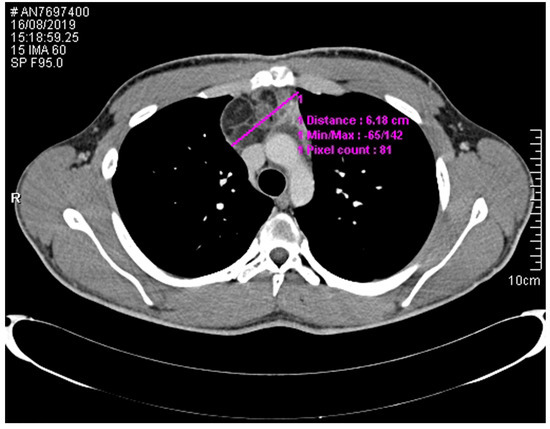

2. Case Presentation